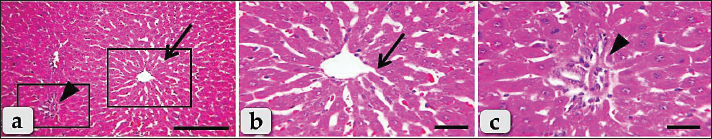

The livers of adult male Wistar albino rats in the control group (G1) were found to be normal, with no abnormalities detected through histopathology. The hepatic parenchyma primarily consists of many typical hepatic lobules. The central vein (Fig. 1a) and portal triad (Fig. 1b) form the center and peripheral boundaries of each lobule, respectively. Hepatocytes, which are the primary cells in each lobule, have a variety of nuclei, including single, spherical, central, and euchromatic, as well as some binucleated cells. Their morphology was irregular and polygonal. Hepatocytes were guided to the outer edges of each lobule by a series of radiations that extended dorsally from the central vein. The hepatic rays that supplied the hepatocytes also contained intact hepatic sinusoids with intact lining epithelium (Fig. 1b). It seemed as though the branches of the bile duct, lymph vessel, portal vein, hepatic artery, nerves, and their lining epithelium were all in good health inside the portal triad (Fig.1c).On the other hand, histological analysis of liver samples taken from the G2; Diclofenac treated group revealed the presence of diffuse coagulative necrotic cells, which had a ghostly appearance, enlarged hepatocytes, hypereosinophilic cytoplasm, and nuclear disappearance (Fig. 2a). The hallmarks of ballooning degeneration, a type of diffuse hydropic degeneration, are enlarged and inflated hepatocytes, pale cytoplasm, tiny pyknotic nuclei, and overall disarray of the hepatic cords (Fig. 2b). The hallmark of this enlargement degeneration was the abundance of vacuoles within the cytoplasm, which could vary in size and shape (Fig. 2b). Figure 2c shows that the central vein was severely dilated and congested (full of red blood cells), and Figure 2d shows that in some areas of the vein, the lining epithelium had severely degenerated, allowing lining cells to slough into the lumen. Hepatic cord pressure atrophy and significant sinusoidal dilatation with congestion were noted (Fig. 2e). In addition, a significant enlargement of the portal blood vessels, acute bleeding, and extravasated red blood cells were observed among the hepatocytes (Fig. 2f, g). In addition to bile duct hyperplasia and extensive vacuolations of the ductal lining epithelium, the portal triad showed significant congestion and blood vessel dilatation (Fig. 2h). Figure 2i shows that many coagulative necrotic hepatocytes encircled severely dilated and crowded blood vessels inside the portal triad, as well as severe inflammatory cell infiltrations, primarily lymphocytes.

Fig. 1. Photomicrographs of the liver of the G1; control group, (a) showing normal, intact hepatic parenchyma without any abnormalities. (b) Higher magnification of the inset box in fig. a showing intact hepatic parenchyma with normal hepatocytes of an irregular polygonal shaped cells with single, central spherical nucleus, and intact hepatic cords (arrow), intact hepatic sinusoids with intact lining epithelium (arrow head), intact central vein (CV) with normal lining epithelium. (c) showing normal and intact portal blood vessels (arrow) of portal triad. Staining: H&E. Scale bars: All=30 μm, except a=200 μm.